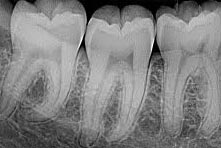

Raio X Digital